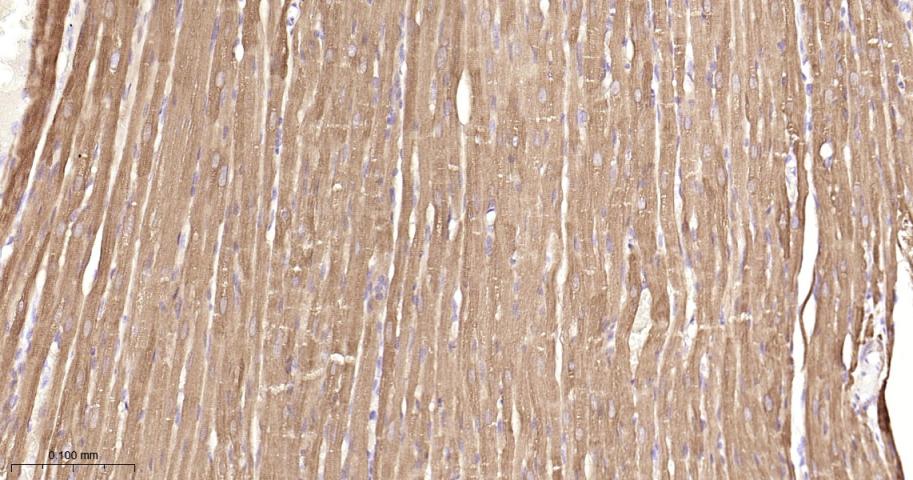

Paraformaldehyde-fixed, paraffin embedded Mouse Heart; Antigen retrieval by boiling in sodium citrate buffer (pH6.0) for 15 min; Antibody incubation with Hsp27 Monoclonal Antibody, Unconjugated(bsm-52757R) at 1:200 overnight at 4°C, followed by conjugation to the bs-0295G-HRP and DAB (C-0010) staining.

Paraformaldehyde-fixed, paraffin embedded Rat Heart; Antigen retrieval by boiling in sodium citrate buffer (pH6.0) for 15 min; Antibody incubation with Hsp27 Monoclonal Antibody, Unconjugated(bsm-52757R) at 1:200 overnight at 4°C, followed by conjugation to the bs-0295G-HRP and DAB (C-0010) staining.

Paraformaldehyde-fixed, paraffin embedded Human Heart; Antigen retrieval by boiling in sodium citrate buffer (pH6.0) for 15 min; Antibody incubation with Hsp27 Monoclonal Antibody, Unconjugated(bsm-52757R) at 1:200 overnight at 4°C, followed by conjugation to the bs-0295G-HRP and DAB (C-0010) staining.